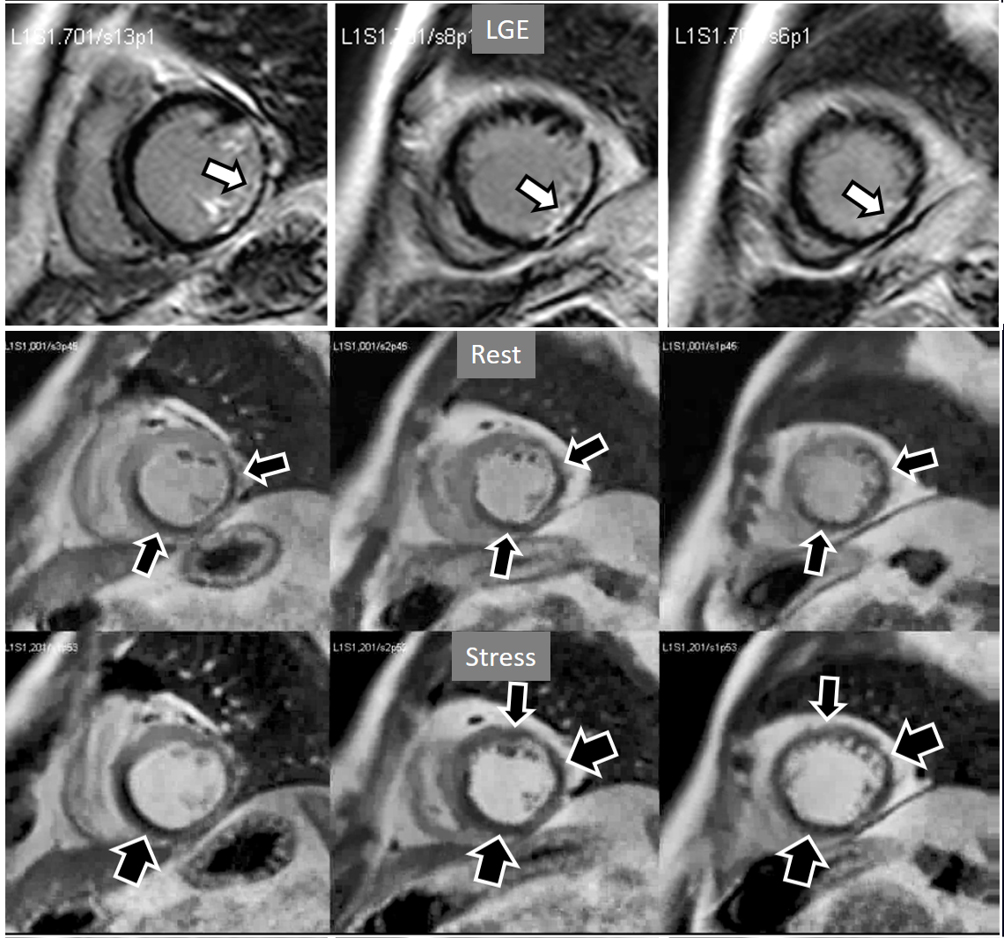

When considering both, the variability of rest perfusion in the presence of previous MI, and the rather low sensitivity of partially reversible defects, the interest in knowing the actual extension of fixed defects emerges. An option to address the issue is to invert the order of perfusion studies in patients with previous MI, performing the rest study first. This allows for a reliable delineation of the fixed defect that can be easily subtracted from the inducible one, when present (Fig. 18). Moreover, in the case of patients with advanced, severe CAD, in whom a combination of infarcted regions and underperfused territories can be expected, a basal rest perfusion study followed by the stress one is even more helpful (Fig. 19). Certainly, the presence of CA in an area of MI after the first rest perfusion study may contaminate the SI of the second one, but this does not preclude the detection, or exclusion, of newly induced defects (Fig. 20).

Fig. 18.Rest/Stress perfusion in chronic myocardial infarction. Patient with previous myocardial necrosis involving most of the LV segments, mainly subendocardial in the anterior and septal regions, and transmural in the lateral wall, as shown in the LGE images (upper panel). The rest perfusion study, performed in first place (middle panel), shows a diffuse subendocardial defect, while, at a subsequent stress study (lower panel), a fair increase in transmurality and extension of the antero-septal defect is seen (arrows) indicating peri-infarction ischemia, while the lateral one remains unchanged. Note the lack of interference of the previous dose of CA on the tissue contrast of the stress study.

Fig. 19.Rest/Stress perfusion in chronic myocardial infarction. Upper panel: LGE study showing subendocardial necrosis of the infero-lateral segments (white arrows). Middle panel: rest perfusion study performed in first place showing a defect extending far beyond the limits of the actual MI (black arrows), indicating impaired perfusion at rest of non-infarcted territories (i.e., myocardial hibernation). Lower panel: subsequent stress study showing an increase in extension and transmurality of the inferior defect (large black arrows) and, also, the appearance of and additional induced defect at the anterior wall (small black arrows). Again, the stress study is not interfered by the previous CA administration.